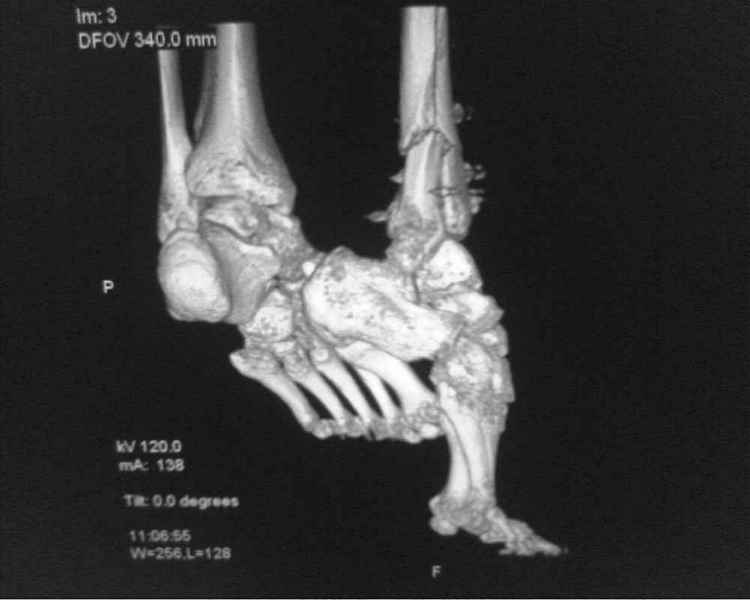

[Ortho] [1/2] Метатарзал краш синдром в порочном сращении (эквинусная стопа), несращение сегментарного перелома костей голени после БИОС , ПТФБ, ХВН СЕАР С-6.

Больной 39 лет. Травма получена в ДТП 21.09.09г. был госпитализирован в обл. больницу

соседней области с диагнозом сочетанная травма зчмт сотрясение головного мозга

сегментарный перелом костей правой голени с\3-н\3, суральный флеботромбоз циркулярные

некрозы н\3 правой голени правого голеностопного сустава лечение скелетным вытяжением за

пяточную кость. переведён в наше отделение 6.10.09г. возобновлено скелетное вытяжение,

перевязки, иссечение некрозов, антикоагулянты. На уздг диагноз флеботромбоза

подтвержден. 28.10.09 операция БИОС правой б\берцовой кости штифтом PTNL остеомед .

остеосинтез м\берцовой кости не выполняли из-за наличия гранулирующих ран и некрозов в

месте операционного доступа. Вторым этапом планировалось наложить аппарат Илизарова для

выведения стопы из эквинуса и динамизации штифта. Но из-за наличия гранулирующих ран и

некрозов в местах проведения спиц на стопе и голени 19.11.09 переведен в ожоговое отделение

для САДП гранулирующих ран после некрозов. 23.11.09 САДП. В послеоперационном периоде-

длительное заживление ран с лизисом кожных лоскутов, манифестное развитие ХВН с

формированием трофических язв и лимфэдемы. Больной явился на госпитализацию 13.01.10г.

локальный статус и свежие снимки прилагаю. Данные уздг выложу позже. Что в этой ситуации

делать я не знаю. Признаков сращения на Rg-нет плюс метафизарный фрагмент кивнул на вальгус.